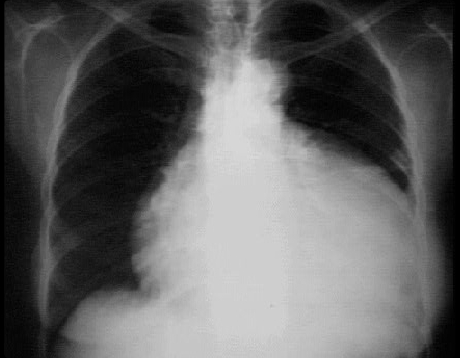

This chest X ray shows a pericardial effusion.

This PA view shows a markedly enlarged cardiac silhouette producing a

water bottle appearance. Note the

neck region of the water bottle formed by the normal aortic shadow.

Note also the normal pulmonary vascularity of the lung fields, an important hint that this enlargement of the cardiac shadow does not reflect underlying chamber enlargement.